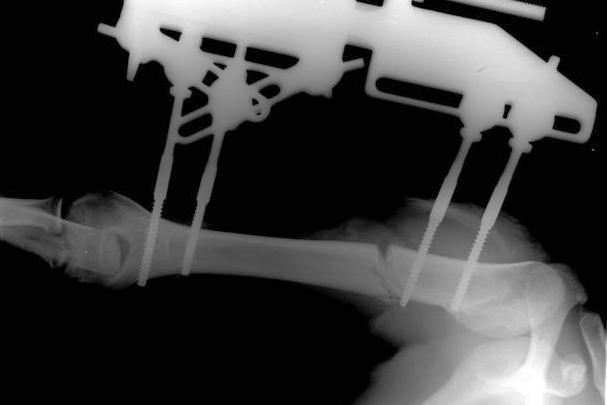

«Мы провели операцию по наложению стержневого аппарата и остеотомию, то есть кость была разрезана пополам, чтобы "новая кость" сформировалась в этом промежутке», — объяснил Григорьев.

Сейчас девушка чувствует себя хорошо. Ее уже выписали домой, но она продолжит наблюдение у травматологов-ортопедов. Металлическую конструкцию удалят из ее руки после полного восстановления кости, в дальнейшем конечность будет развиваться и расти нормально, уточнили в Минздраве.